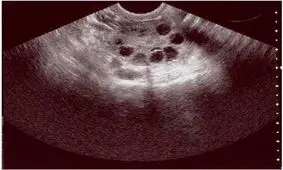

فیبروم های رحمی توده های خوشخیمی هستند که در رحم رشد میکنند و معمولا سرطانی نمی شوند.

فیبروئیدهای رحمی تودههای غیرسرطانی هستند که در ناحیه رحم رشد میکنند، این اختلال در بسیاری از زنان شایع است.